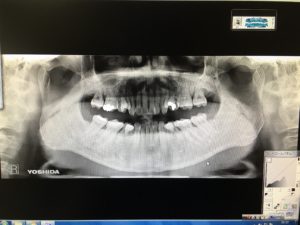

初回の内容は、レントゲン撮影、歯周病検査、口腔内写真、口腔内スキャナーの4つの検査をさせていただきます。

レントゲンとAIによる初期むし歯チェック装置による検査及び結果説明。